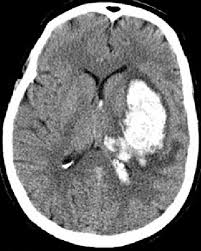

Brain Scan

Brain scan: Black = ischemic stroke, white = hemorrhagic stroke. Source

Chronometric age of the brain lesion is a critical parameter clinicians use to assess the types of interventions a patient may benefit from receiving. The best contemporary method for treating acute stroke, administering tissue plasminogen activator (tPA) to break blood clots in the brain, is only effective within the first 4.5 hours post-stroke. Similarly, surgical interventions have been shown to be more effective in the first 6 hours post-stroke compared to 6-24 hours post stroke.